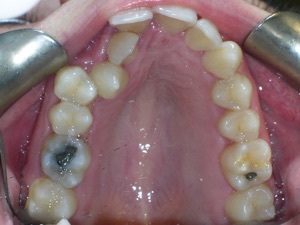

This case was of a young lady who desperately wanted Invisalign, but had been told it was not possible. There was not one, but two teeth that had come in toward the roof of the mouth.

Here are some progress photos.